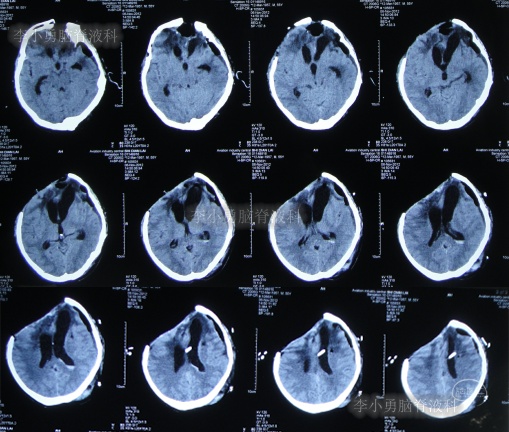

继续治疗1个半月,期间4次(2013年2月15日、2013年2月27日、2013年3月5日、2013年3月11日)查头颅CT(图-19、图-20、图-21、图-22)均示脑室在不断的变好。

图-19:2013年2月15日头颅CT

图-20:2013年2月27日头颅CT

图-21:2013年3月5日头颅CT

图-22:2013年3月11日头颅CT

2013年3月12日(入院治疗132天),拔除了头部外引流管(图-23)。

图-23:2013年3月12日头颅CT

2013年3月15日(入院治疗135天),查头颅CT示脑室周水肿减轻(图-24)。

图-24:2013年3月15日头颅CT